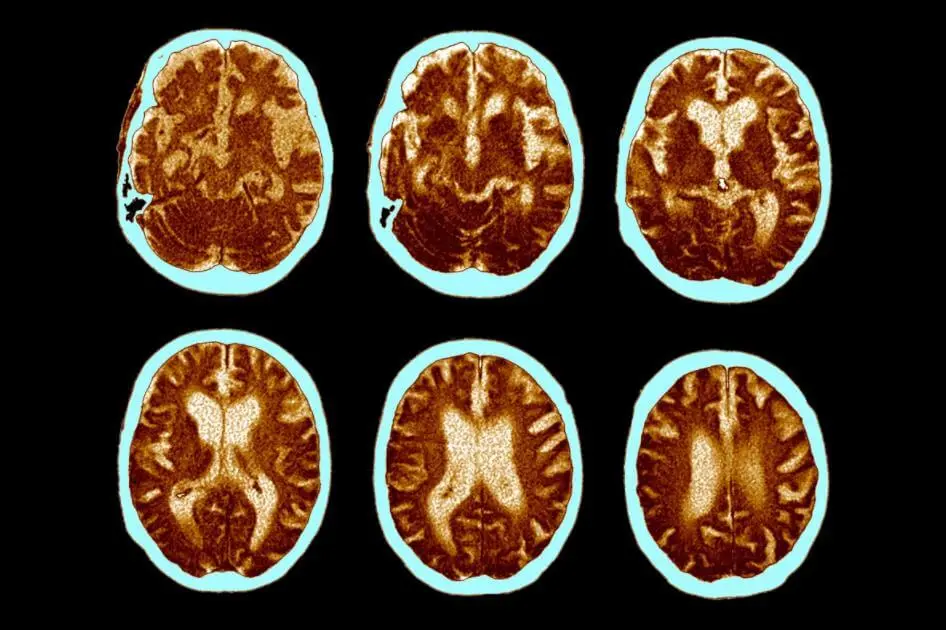

How dementia develops

Above:A 68-year-old woman with a 10-year history of cognitive impairment showed marked hypometabolism with a pattern suggestive of Alzheimer's disease prior to PET scan, PET scan after treatment with inhibitor (RI). Gradually approaching the normal brain, the patient's cognitive ability improved significantly.